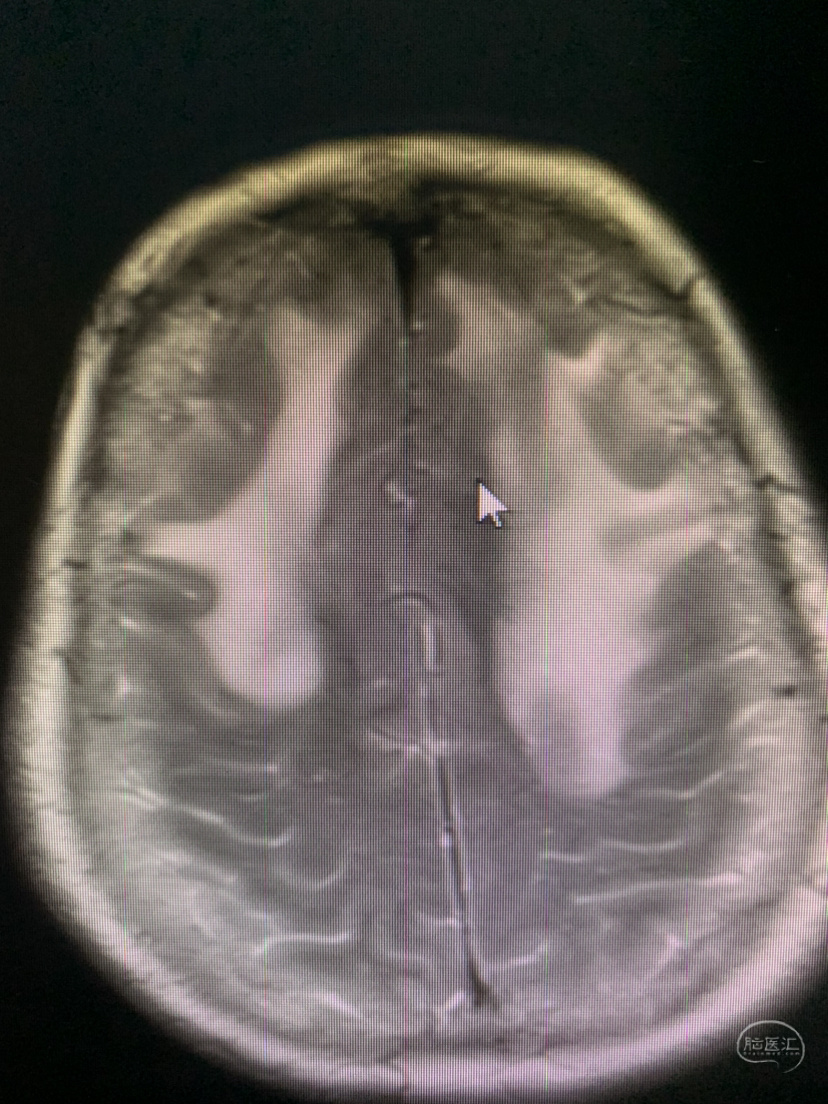

术前术后对比